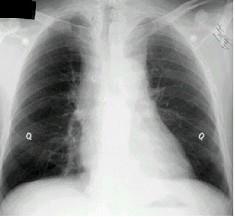

问题 男,26岁,自觉肌无力2周,胸片检查见纵隔增宽,CT检查如,最可能的诊断为 ( )

选项 A.上纵隔畸胎瘤 B.胸内甲状腺瘤 C.中纵隔胸腺瘤侵犯血管 D.淋巴瘤侵犯血管 E.下纵隔畸胎瘤

答案 C